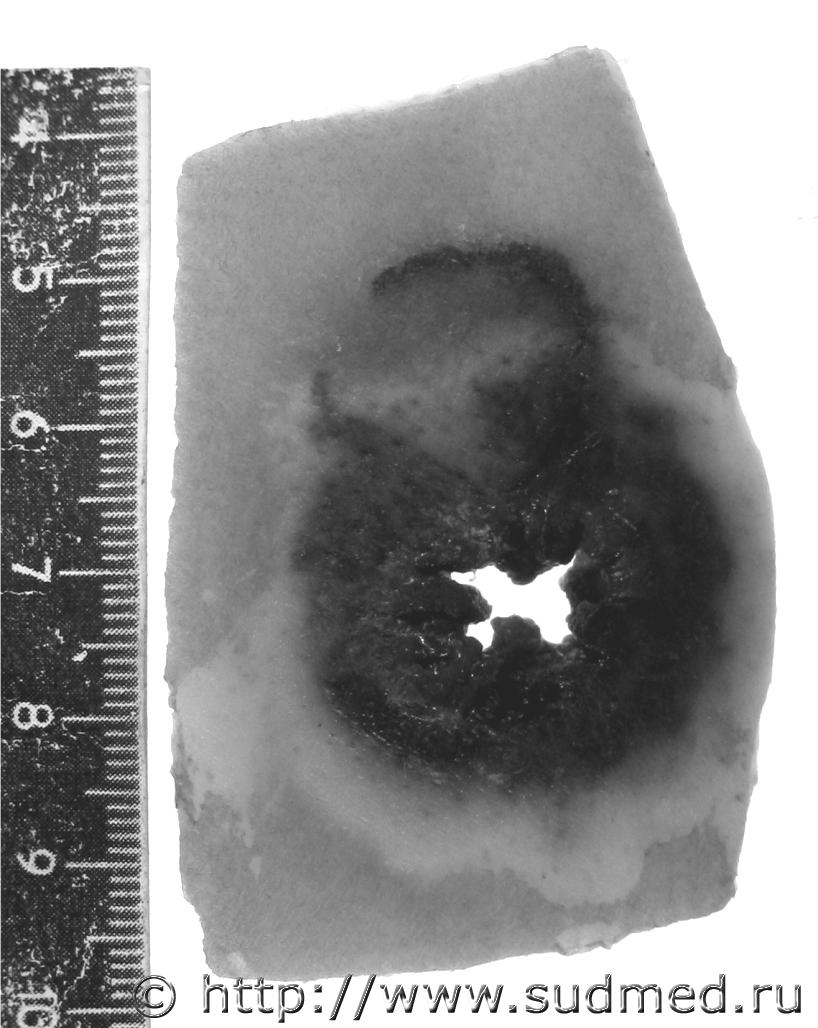

Кальцификат в толще левой широкой связки матки.

Судебная медицина - Прикрепленное изображение Судебная медицина - Прикрепленное изображение